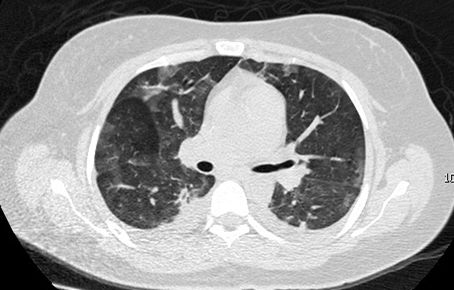

复查胸部CT提示双肺多肺叶实变影(图2)

图2:肺部CT(2017-08-29)

血气分析提示(面罩吸氧,具体吸氧浓度不详)pH 7.45,PCO2 28mmHg,PO2 51mmHg,HCO3- 22.1mmol/L,BE -4.5mmol/L,cLac 1.1mmol/L,SO2 88%,故为进一步诊治收入RICU。